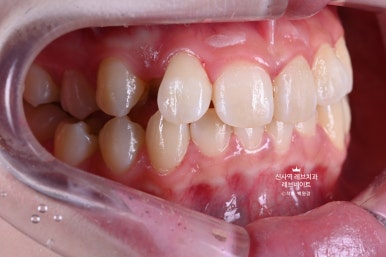

오른쪽 송곳니가 보다 안쪽에 있는 부정교합이라, 마치 치아하나가 없는 것 처럼 보이는 상태셨어요.

크라운치료를 하자니, 송곳니가 있어서 송곳니를 무조건 뽑아야 했고...

옆에서 보면 어색하지만 앞에서 보면 착시효과가 있어 치아 형태가 아주 그럴싸 해보인다는 것입니다.